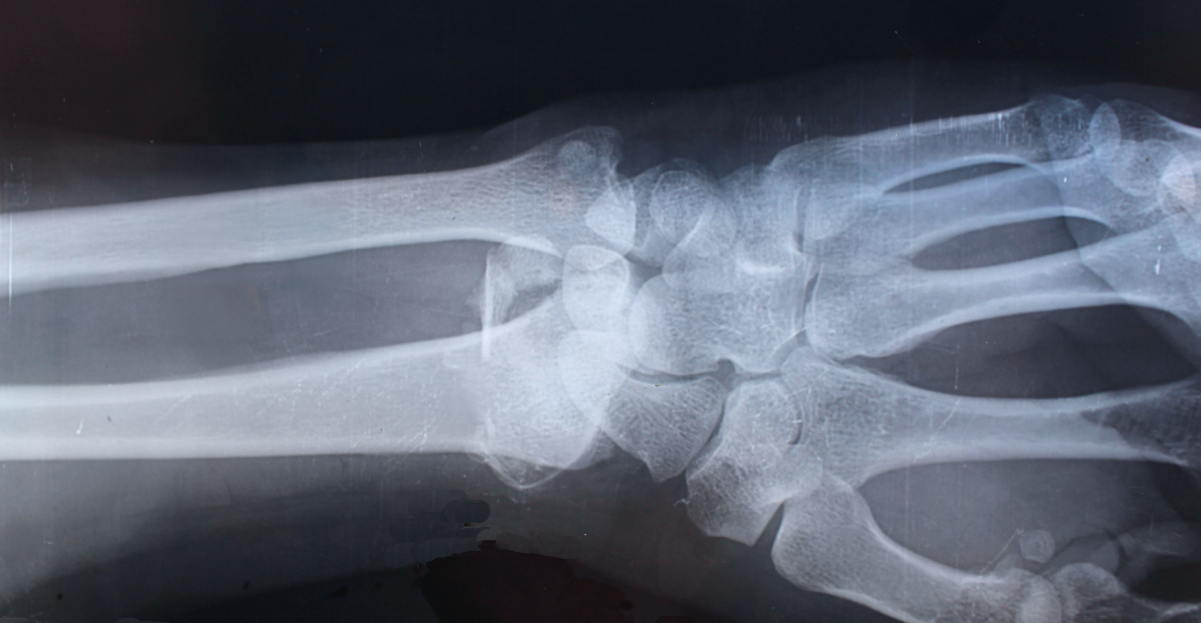

Osteoporosis occurs when your bones become less dense and start losing minerals like calcium, making them more fragile. Healthy, strong bones help anchor your body for movement, meaning you are less likely to lose your balance.

When you live with osteoporosis, not only are you more likely to fall over, you are more likely to fracture a bone when you fall or complete everyday tasks. Unfortunately, declining bone health can also put you at risk of back pain and compromised posture, and lead to psychological consequences such as anxiety, depression, social isolation and a reduced sense of self-worth.